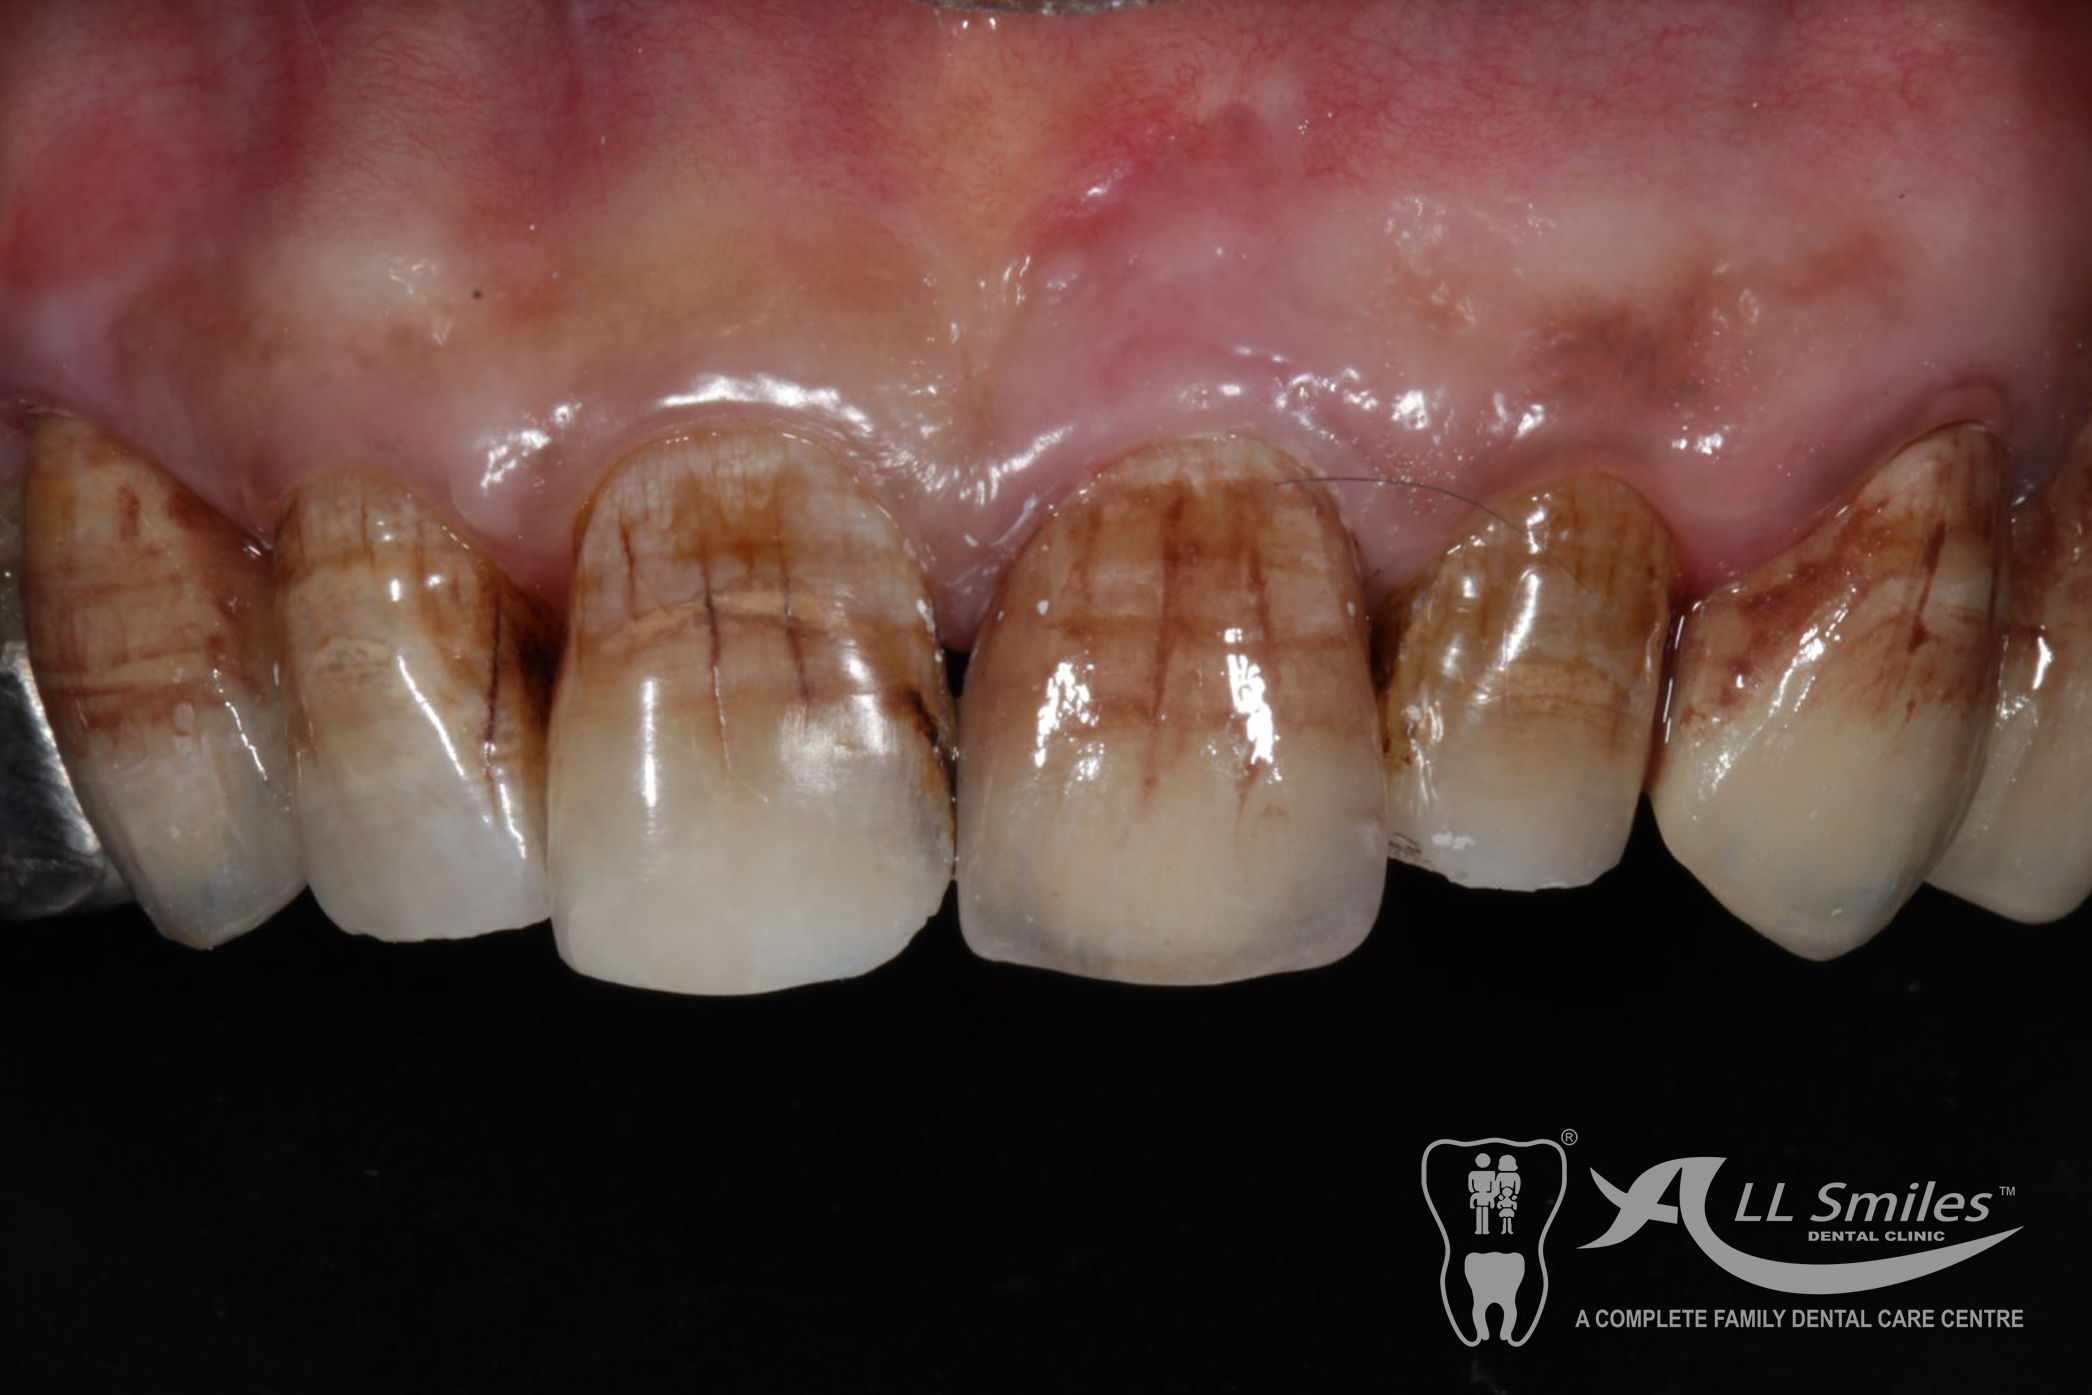

Crowns & Bridges Gallery